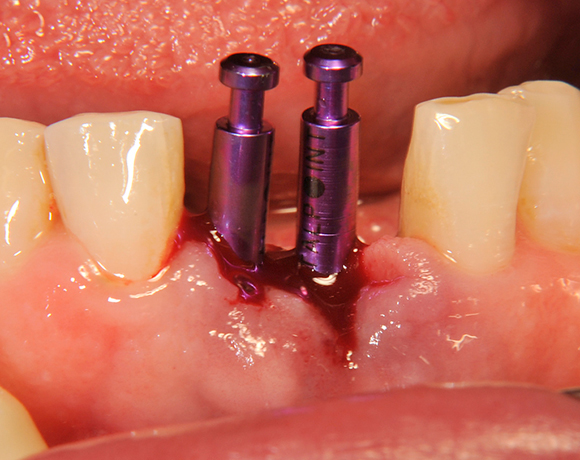

Zwei Unterkieferfrontzahn – implantate

Die Keramikimplantate der Fa. Dentalpoint lassen sich auch zur Sofortimplantation verwenden. Das bedeutet, dass nach Extraktion nicht beherdeter Zähne direkt die Implantate gesetzt werden können.

Im vorliegenden Patientenfall wurden die beiden nicht erhaltungswürdigen, mittleren Unterkieferschneidezähne durch zwei Vollkeramikimlpantate ersetzt.